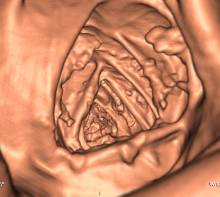

Рисунок 1.

Эндоскопическое окно при виртуальной колоноскопии. Некачественная подготовка.

Пристеночное резидуальное содержимое симулирует полиповидные образования.